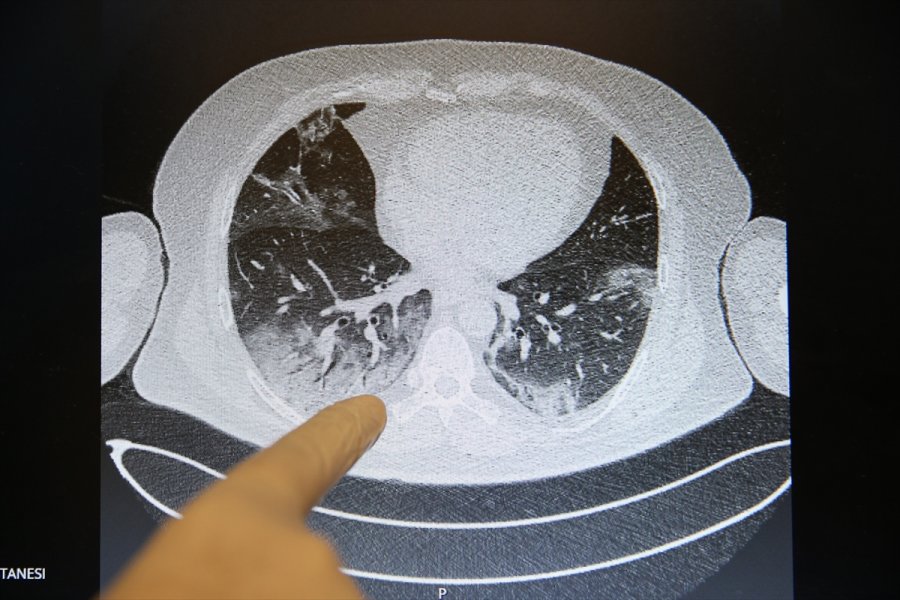

Görüntülerdeki beyazlıklarla Kovid-19'lu bir hastanın akciğerindeki tutulumlar, iltihap birikmeleri ve organın yapısının bozukluğu ortaya konuluyor. Normal hastaların ise akciğerindeki elastik yapı dikkati çekiyor.

Elastik yapıya sahip akciğerlerde Kovid-19 nedeniyle oluşan tahribatlar sonucu zaman zaman organın kapasitesi küçüldüğü için hasta iyileştikten sonra da nefes almakta güçlük çekip, yürümekte zorlanabiliyor.

"Elastik bir yapısı olan akciğer dokusunda sertleşme ve yapısında bozulma olabiliyor. Bu hastalık geçen yıl kasımda ortaya çıktı. Hastalarımızı daha bir yıl bile takip edemedik. Türkiye verilerini daha mart ayında aldık. Uzun dönemli etkilerini dünya bilmiyor ama bazı yayınlar şunu gösteriyor; Kovid-19 hastalığını kapan ve akciğer tutulumu olan bazı bireylerde ileri dönemlerde fibrozis (akciğer sertleşmesi) dediğimiz bir tablo oluşuyor. Akciğer dokusu elastik bir yapı, genişlemeye ve büzüşmeye müsait bir organ. Koronavirüs nedeniyle akciğerde fibrozis gelişince büzüşme ve genişleme olmuyor. Bu yüzden akciğer kapasitesi ve kişinin efor kapasitesi azalıyor. Eski fonksiyonel kapasitelerine dönemiyorlar. Bu ne kadar hastada oluyor, niye bazılarında oluyor bunu henüz bilmiyoruz."